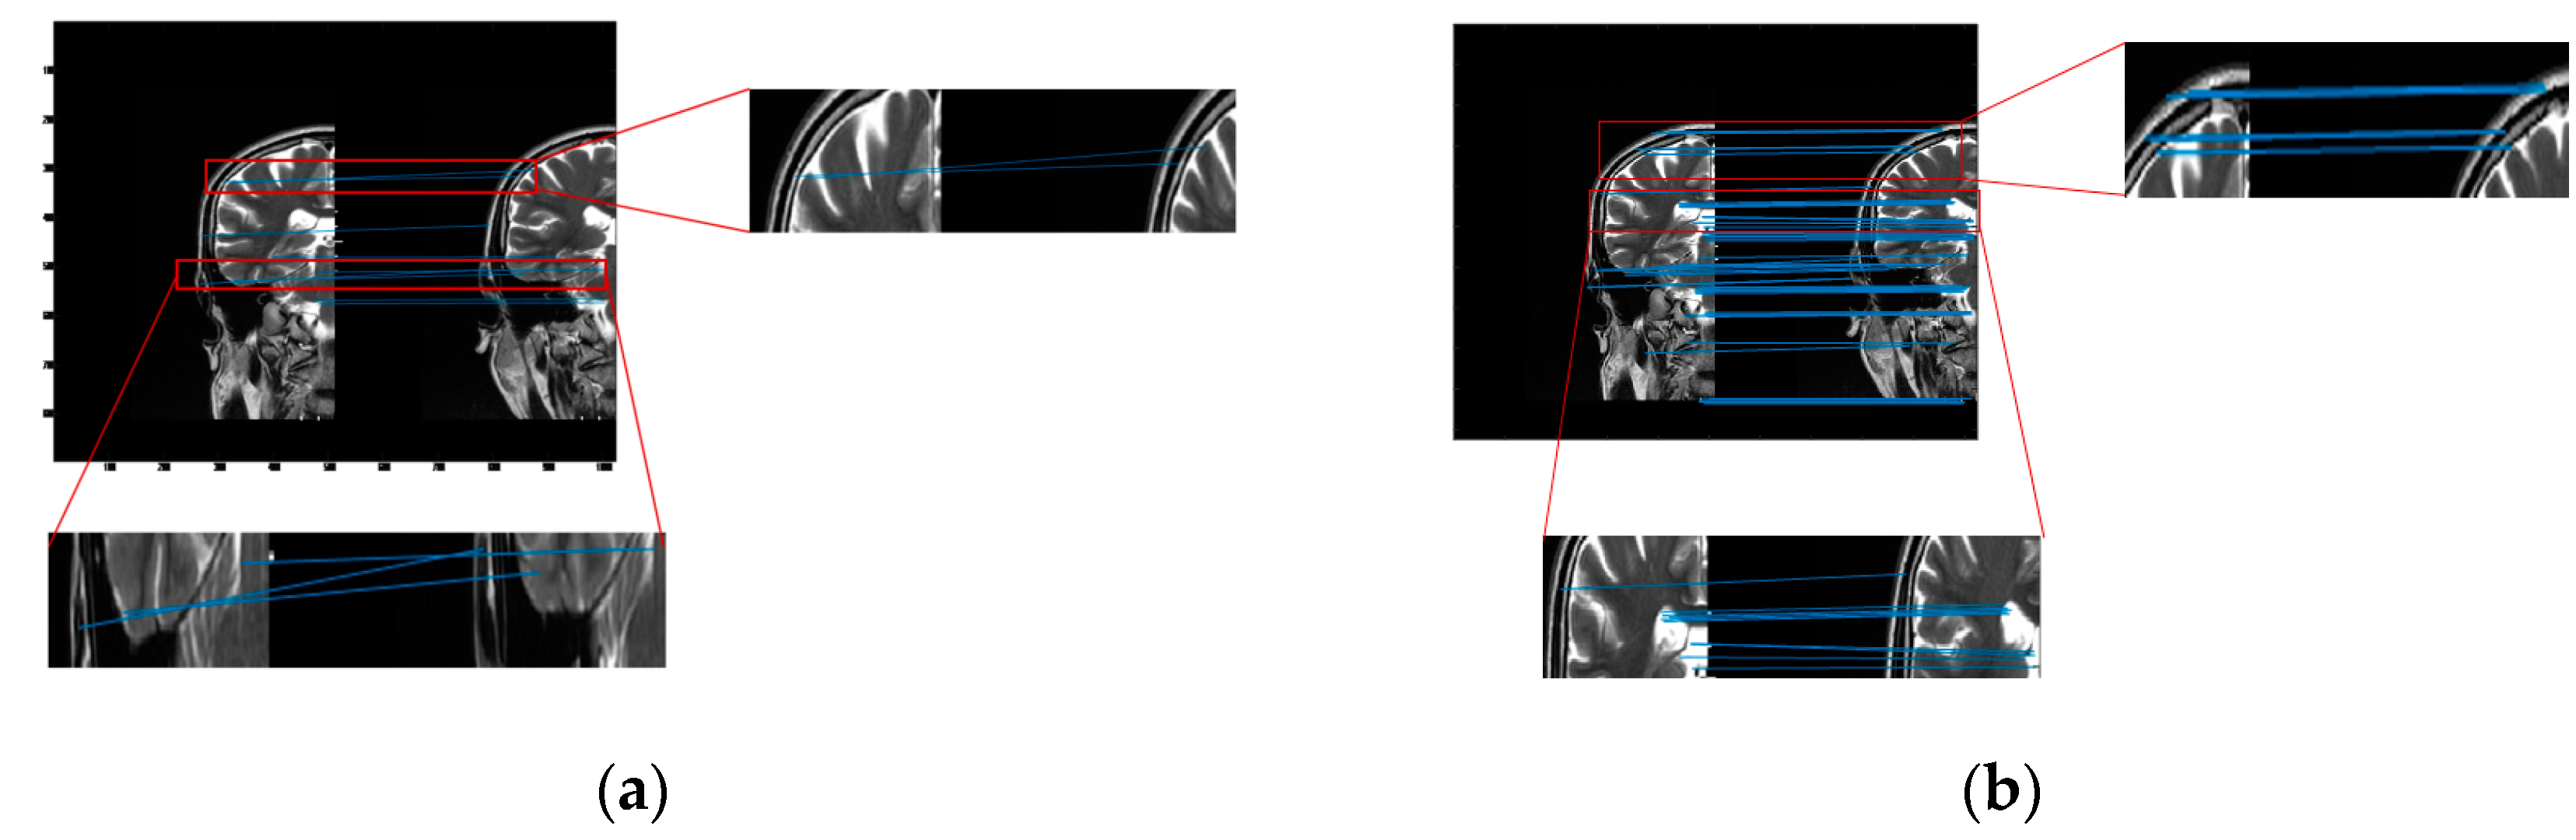

The cross-sectional images of the brain are piecewise smooth, and common registration algorithms are prone to false connection points (as shown in Figure 4a). As we can see from the images, the tissue usually does not follow any particular direction. Throughout the image, the tissue structures continually change direction, creating curved edges. For piecewise smooth medical images, the curvature becomes an important parameter to describe and characterize. Bendlet transform can achieve curvature classification by adding bending elements.

Figure 4.

The Experimental results of image registration between two brain hemispheres (a) The registration result of SURF algorithm. When the SURF algorithm is applied to medical images, the feature points obtained are few and contain more misalignment points. (b) The registration result of the proposed method. Our method increases the number of registered points and reduces mis-matched points.

We transformed cross-sectional images of the brain to the frequency domain via Bendlet, analyzing the transformation coefficients at each scale. When the bending elements coincided with the curvature of the image, the coefficient response was very large, and contour information could be extracted from medical images by Bendlet. We introduced bending elements in Bendlet as registration elements to describe medical images at multi-scales and multi-directions. When the bending element was consistent with the curvature of the image, the point with large coefficient response was found as the registration point. Then, stable points at different scales were selected, and feature vectors were constructed to realize image registration and correction. As shown in Figure 4, our method had more connection points and no mismatch points.